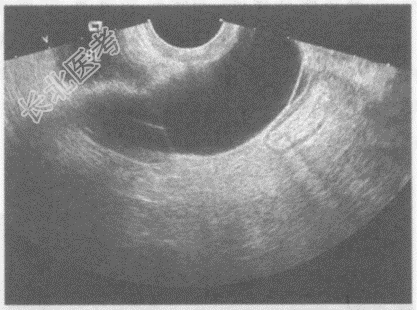

- 单项选择题临床资料:女性患者, 41岁,子宫全切术后。妇科内诊: 盆腔可触及肿物,质软。

超声综合描述: 经阴道扫查左附件区可见腊肠样无回声区,内透声清亮。

超声提示:  A、左卵巢囊肿

B、盆腔包裹性积液

C、左输卵管积水

D、左卵巢巧克力囊肿

E、左卵巢冠囊肿